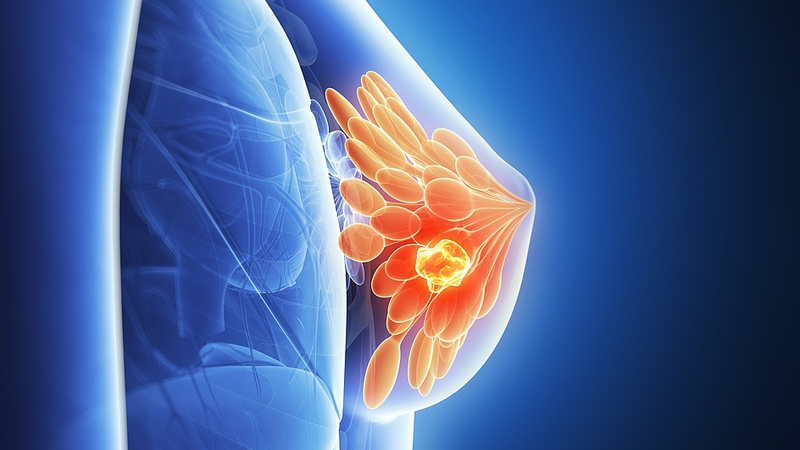

Hey everyone! Researchers from the Weizmann Institute of Science in Israel have uncovered a fascinating process where breast cancer cells enter a 'sleep mode,' hiding in the body for years before reawakening. Think of it like your favorite app going into standby mode, only to surprise you later with a burst of energy! 😮

The study reveals that these cells mimic a natural cycle normally seen in healthy breast tissue, where cells shift from a rapid growth phase to a more stable, mature stage. By boosting levels of a protein called OVOL, researchers managed to put the highly aggressive triple-negative breast cancer cells into dormancy. In experiments with mice, this approach slowed down tumor growth, offering promising clues for future treatments.

However, there's a twist. While OVOL helps suppress cell division initially, its decline—possibly due to hormonal changes like lower estrogen levels—could trigger a dangerous reawakening of the cancer cells. Additionally, the dormant cells accumulate unstable molecules called free radicals, which can damage DNA and compromise the cell's repair systems, making the disease harder to treat once it returns.

This breakthrough adds a new dimension to cancer research by emphasizing the importance of the dormant stage. Understanding this process could pave the way for therapies that prevent cancer from making a comeback, even years after remission. Stay tuned for more updates on this exciting development! ✨